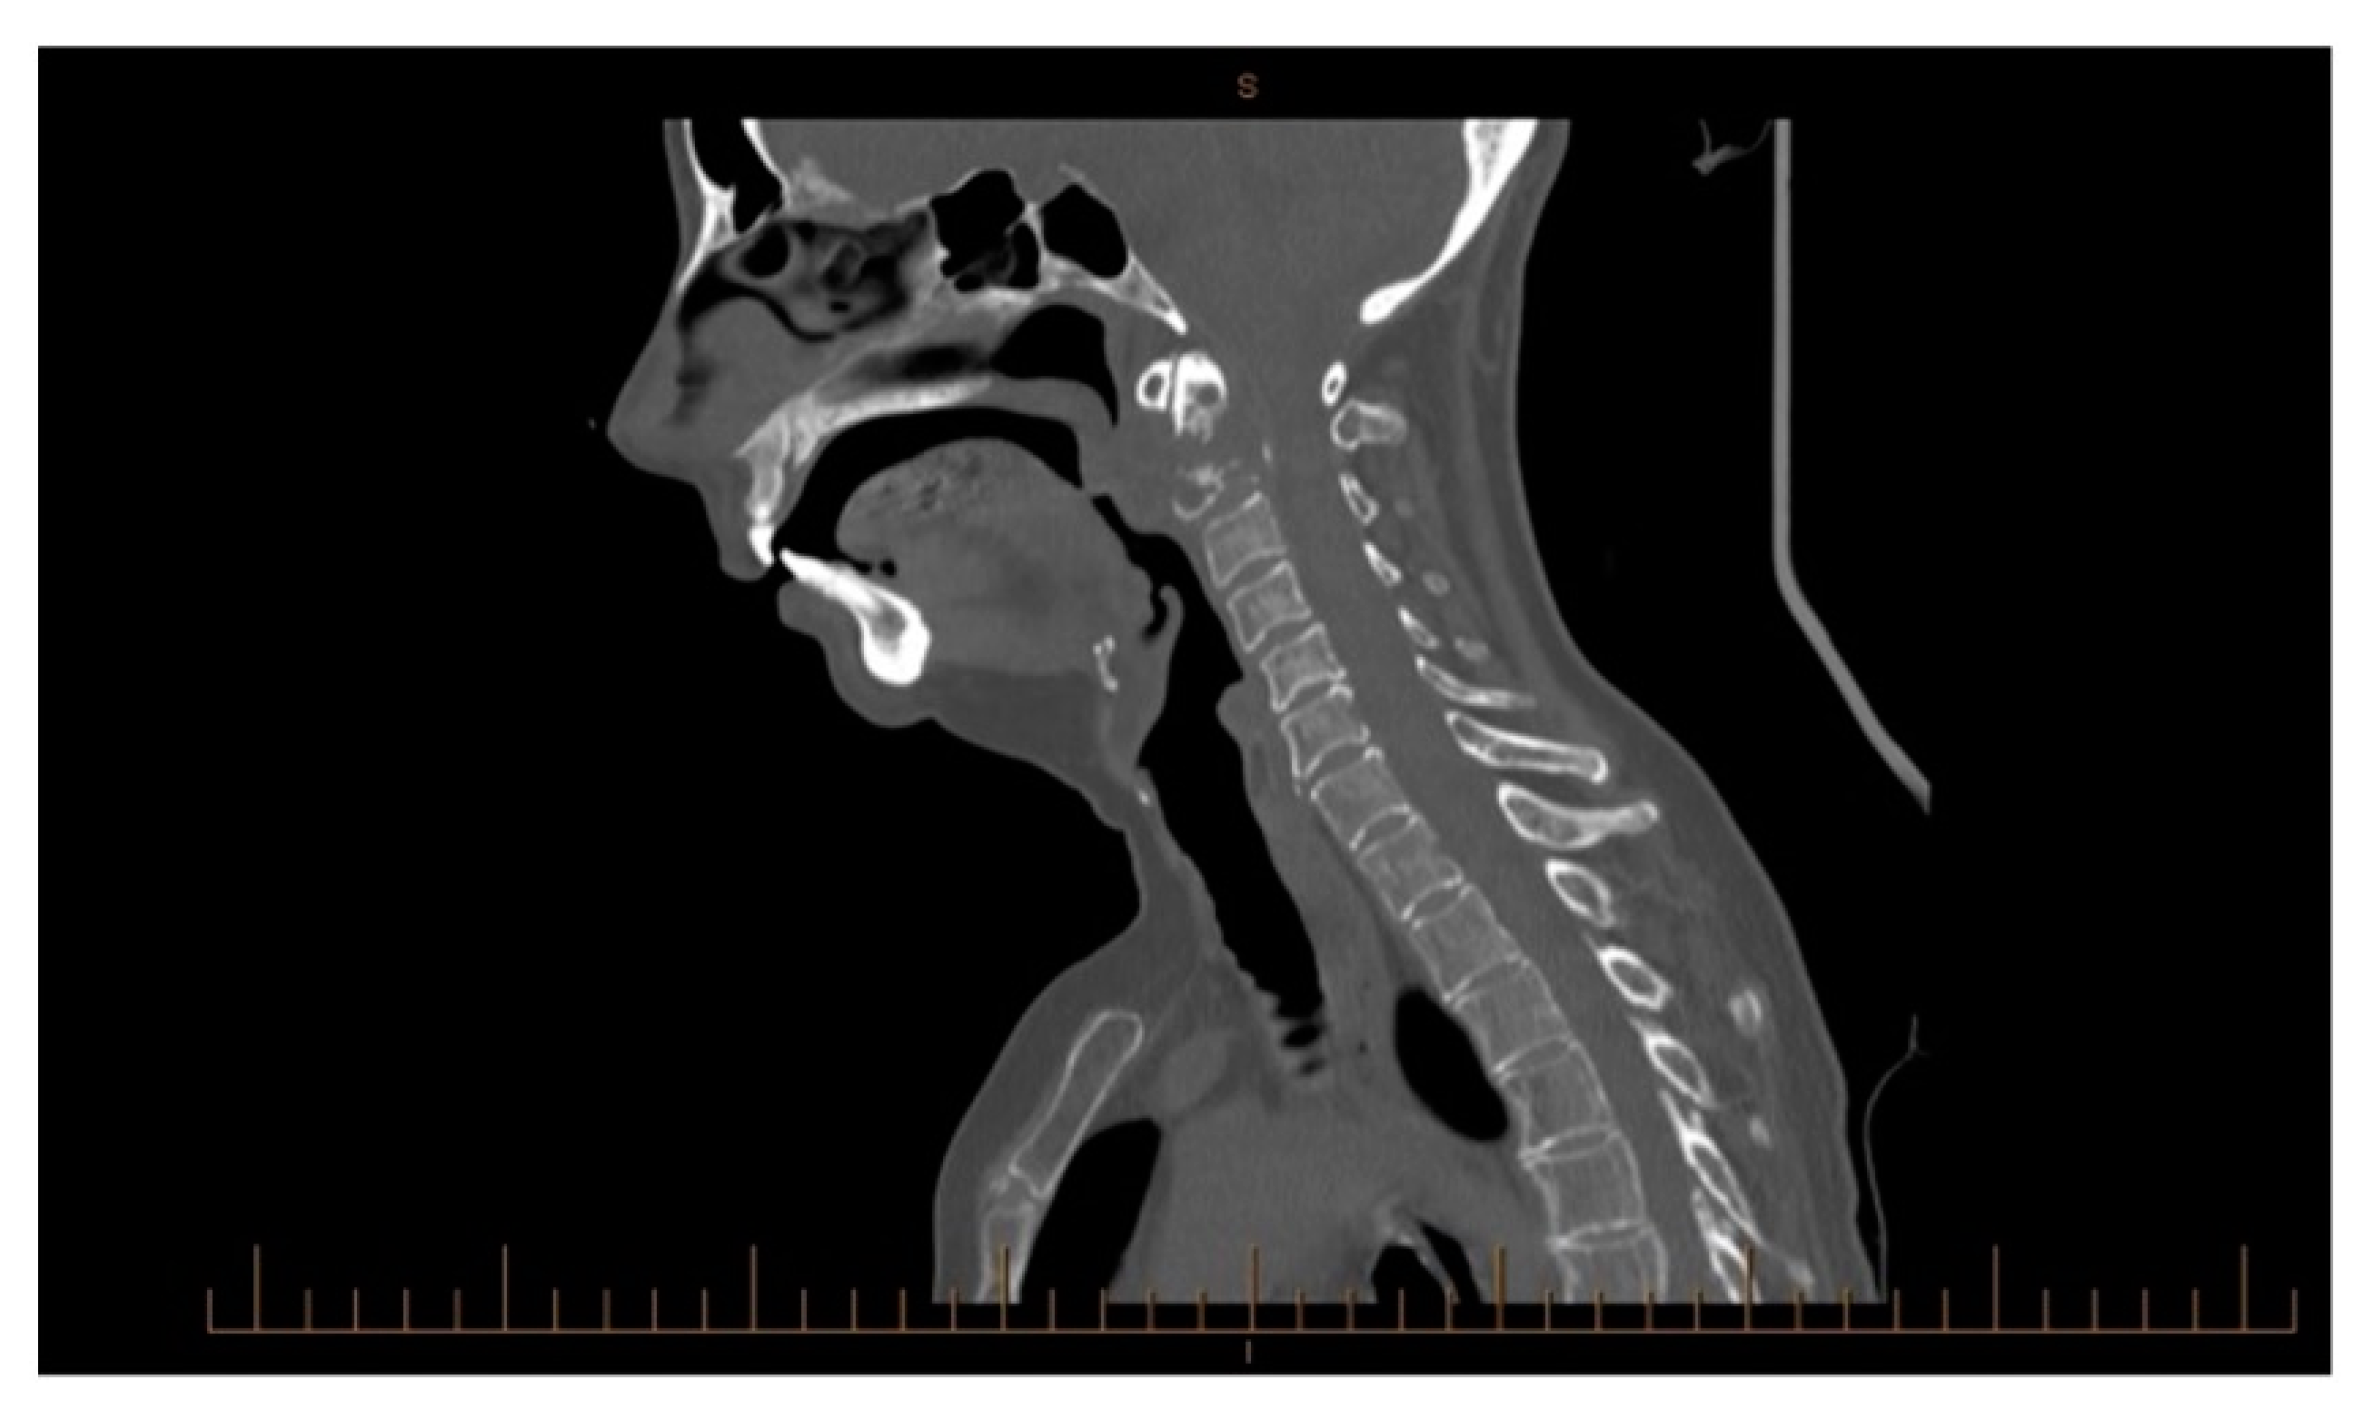

3.1.2. Imaging and Classification

3.1.3. Treatment